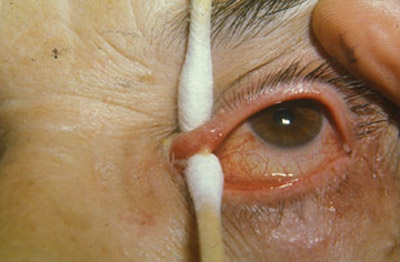

La presencia de un canalículo superior o inferior eritematoso, turgente, a veces doloroso, lleno de abundante material purulento caseoso, de color verde claro, caracteristicamente producido por estos microorganismos, nos lleva al diagnóstico.

El punto lagrimal inferior puede estar vertical, en un ligero ectrópion medial. Al realizar presión sobre el canalículo afectado entre dos hisopos de algodón, y repitiendo esta maniobra varias veces en la lampara de hendidura, se puede obtener abundante material caseoso sin dificultad.

Hemos intentado abolir la marsupialización, practicando con éxito un tratamiento que consiste en hacer una expresión suave del canalículo afectado con dos aplicadores de algodón, uno colocado en la porción más nasal del fondo de saco conjuntival y el otro sobre la piel , tratando de evacuar la mayor cantidad de material caseoso contenido en la luz canalicular.

Luego se realiza un lavado lagrimal con jeringa y cánula, aplicando 2 cc. de Penicilina G. Cristalina. El procedimiento es repetido cada tercer día, hasta cuando no salga más material y se solucione la infección y la epífora. Estos lavados se prolongan por espacio de un mes, en promedio. Así se cura el proceso infeccioso y se evita el daño canalicular y la epifora residual.